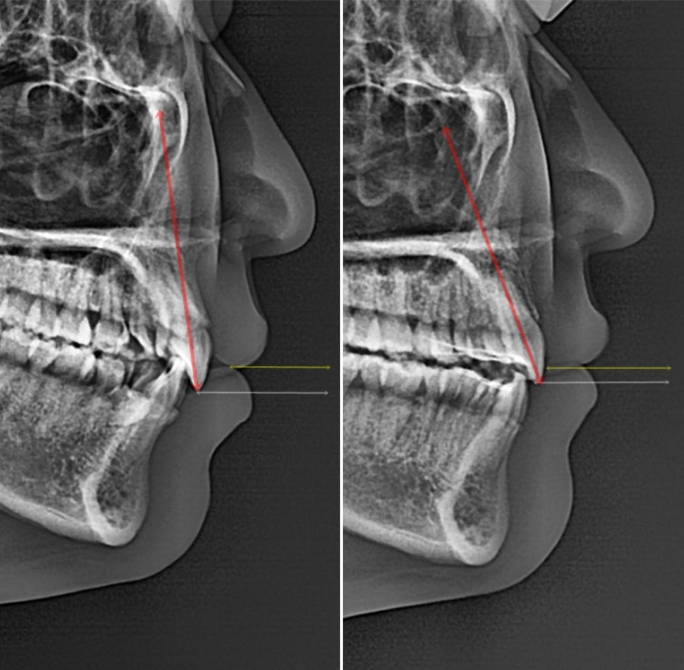

23.08~25.11

치료 전 후 엑스레이 중첩을 보면 위 앞니가 약 2mm 뒤로 들어갔고 옥니 각도의 개선이 보입니다.

또한 거미스마일 개선을 위해 위 앞니가 상방으로 약 2mm 함입되었음이 확인이 됩니다.

거미스마일 교정에서 앞니 합입량의 기준은 얼마일까에 대해서는 아래 포스팅 참고해주세요

간단히 정리를 해보자면 너무 많이 올리면 앞니 뿌리에 치근흡수 위험도 높아지고 평소 말할때 윗니가 너무 안 보이고 아랫니만 보이게 될 수도 있으니 적정수준을 목표로 합입해야 한다는 내용입니다.